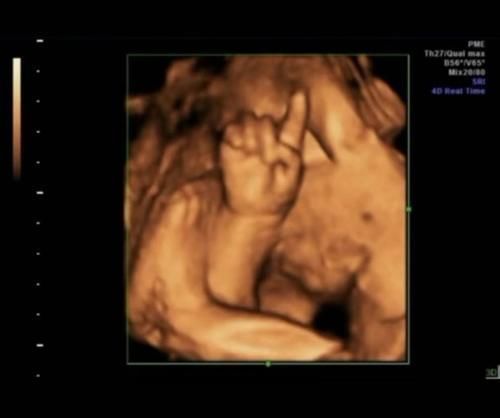

原来,小刘每次做4D都会拍照。这是小刘第四次做4D。她取出先前4D照片中的照片,发现小男孩每次在其中做出不同的手势,将它们连接在一起。碰巧是“ 1234”。

小刘觉得这是孩子自己记录的4D数量。医生还开玩笑地说:“看来这个孩子可能是下一个数学天才。”